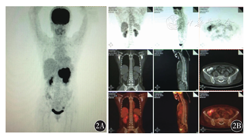

例1,以上腹部不适起病,行胃镜检查后诊断为NHL,后行骨髓检测,骨髓涂片、骨髓活组织检查均阴性(图1),骨髓流式细胞术检测及PET-CT均未明确淋巴瘤骨髓浸润(图2),但骨髓免疫病理检测结果示:骨髓增生大致正常(50%),少量异型淋巴细胞呈小簇状或散在分布(占有核细胞比例<0.02),胞体大,胞质少,核圆形或略不规则,部分细胞可见核仁。结合免疫组织化学检测CD20、PAX-5、MUM-1、c-myc均为阳性,明确诊断为弥漫大B细胞淋巴瘤(DLBCL)骨髓浸润(图3)。

例2,以颈部淋巴结肿大起病,行淋巴结病理活组织检查后诊断为血管免疫母细胞性T细胞淋巴瘤,后行浅表淋巴结彩超、肺部CT、腹部CT,分期为Ⅲ期,进一步行骨髓涂片、骨髓活组织检查,均阴性(图4),但骨髓免疫病理检测结果示:骨髓增生较活跃(60%~70%),一类异型淋巴细胞呈散在或小簇状分布,胞体中等偏大,胞质丰富,核圆形或略不规则,部分细胞可见核仁;偏成熟阶段粒、红细胞散在分布,巨核细胞较多,分叶核为主,网状纤维染色(MF)1级。结合免疫组织化学检测CD2、CD3、CD5、CD7均为阳性,明确诊断为血管免疫母细胞性T细胞淋巴瘤骨髓浸润(图5),并纠正临床分期为Ⅳ期。